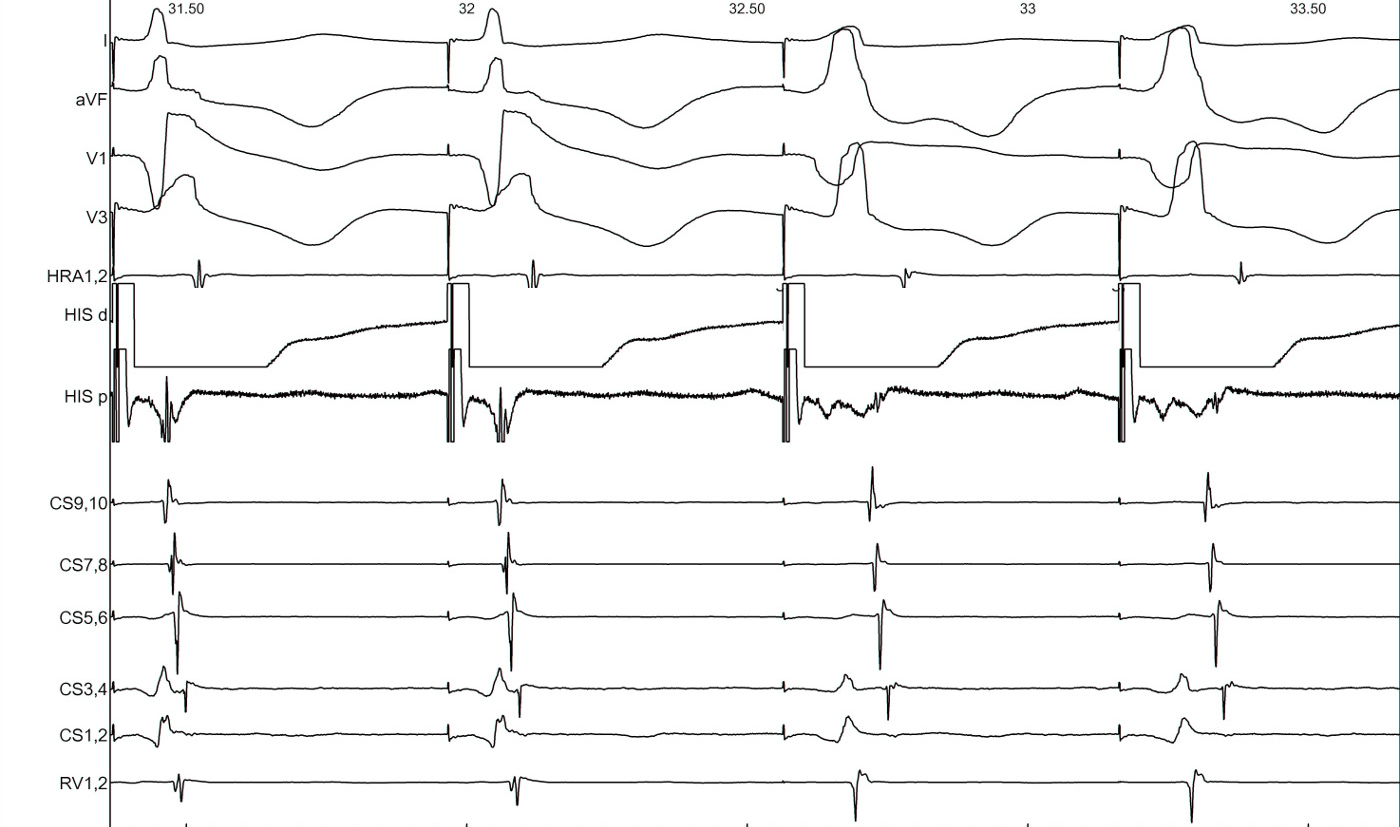

Parahisian pacing

Parahisian pacing - setting up

• His catheter, slightly pushed in (small A)

• Start with low output and increase gradually

• Watch QRS morphology for intermittent His capture

Parahisian pacing - interpretation

• His capture - narrower QRS, His not seen, RVA early

• Beware of atrial capture

• Beware of pure His capture

• Narrower QRS

• Isoelectric interval from pacing spike to QRS

• Identify beats with and without His capture

• Look at atrial activation sequence

• Measure VA interval

Parahisian pacing - with His capture

• Nodal conduction - same sequence, shorter VA

• AP conduction - same sequence, same VA

• Mixed response - different sequence, shorter VA